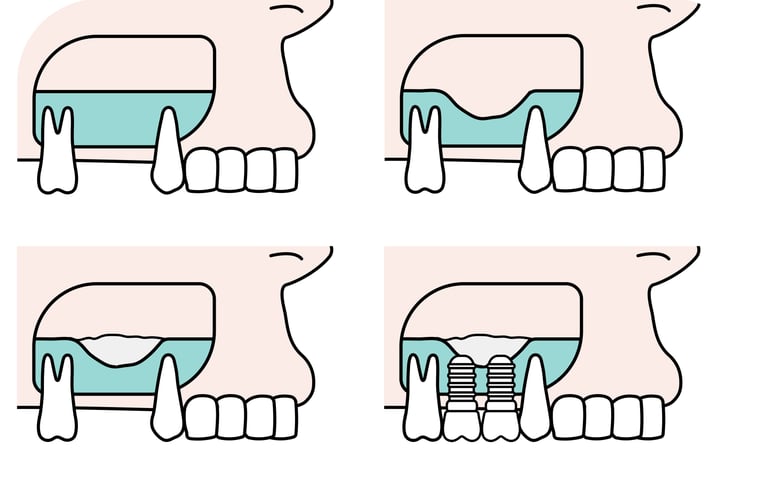

Es un procedimiento para añadir hueso a al maxilar superior en la zona de los molares y premolares, elevando el suelo del seno maxilar para permitir la colocación de implantes.

Elevación del Seno Maxilar